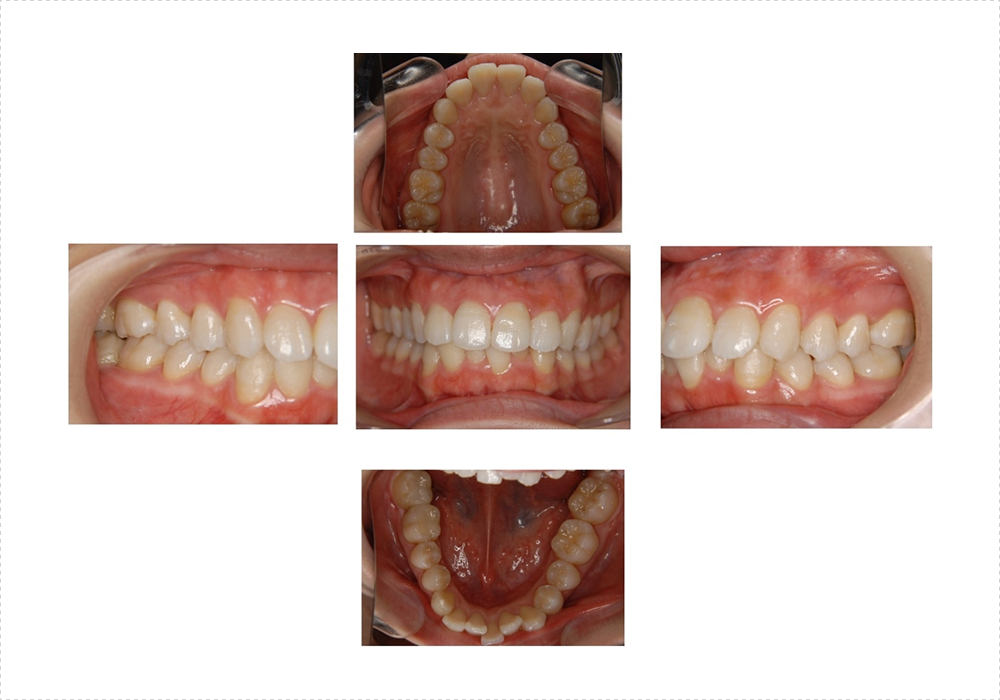

口腔内写真

歯や歯茎の色など今の状態を記録します。